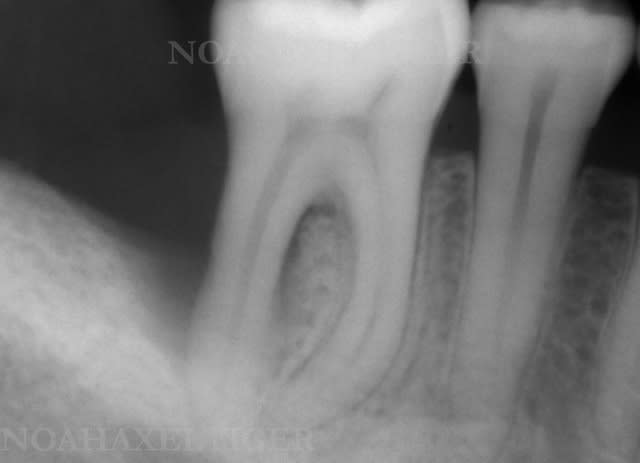

Cas 2 (parodontite aggressive sur une jeune fille de 13 ans)

Photos initiales c6c2bg - Eugenol

Bilan initial nhvmno - Eugenol

Photos  1an drrxtl - Eugenol

Comparaison bilan rx bix6qa - Eugenol

Bilan de sondage  1 an muiwyr - Eugenol